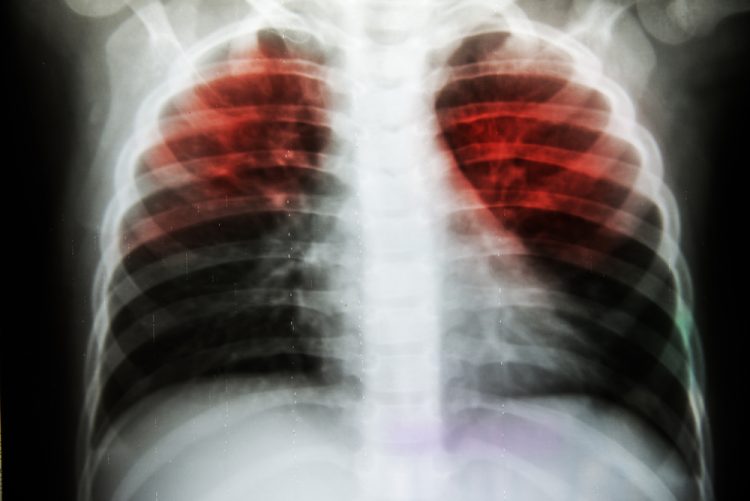

New AI method maps how tuberculosis drugs destroy bacteria

Scientists at Tufts University have developed an AI tool that demonstrates how tuberculosis drugs kill bacteria – an advancement that could speed-up the discovery of shorter, more effective treatments.